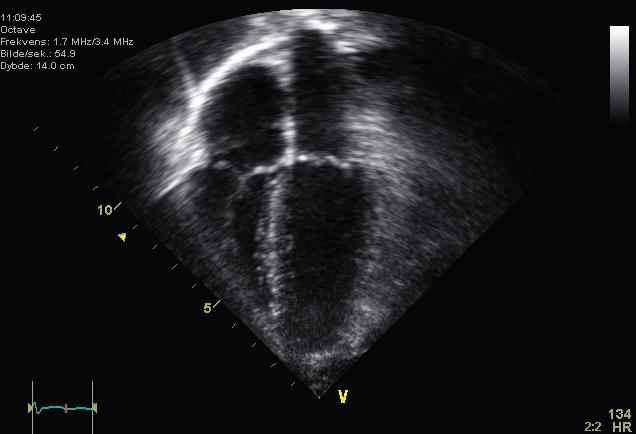

An echocardiogram (ECG) is an ultrasound of the heart that is used to determine if the heart valves and muscles are working correctly. In this photo, all four chambers of the heart can be seen.

This is an ultrasound picture of a normal heart showing all 4 chambers.

Figure 31.15 (credit: Kjetil Lenes, Wikimedia Commons)